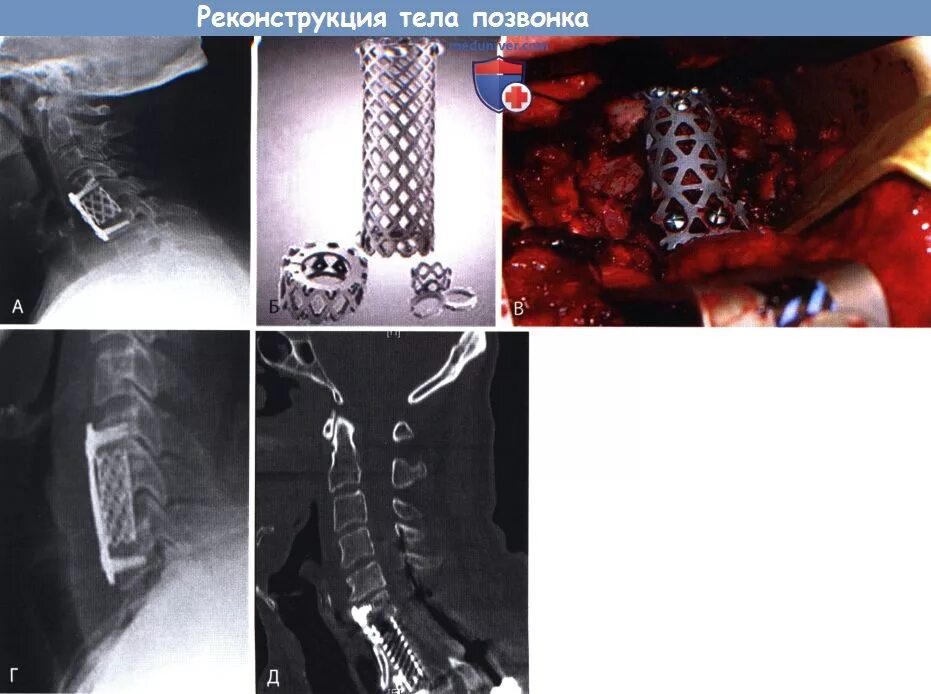

Установка кейджа в позвоночнике